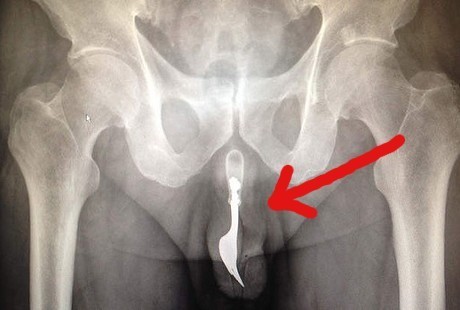

Jakarta - Serang pria di Canberra, Australia dilarikan ke Unit Gawat Darurat (UGD) dengan keluhan yang terbilang tidak lazim. Garpu sepanjang 10 cm masuk tersangkut di saluran kencing dan menyebabkan sakit yang luar biasa pada batang penisnya.

Pria 70 tahun yang tidak disebutkan namanya ini masuk UGD dengan keluhan perdarahan pada organ genital. Dokter melaporkan, sebilah garpu terjebak di saluran kemih setelah dengan sengaja dimasukkan oleh si pria 12 jam sebelumnya untuk keperluan masturbasi.

Karena terjebak di dalam, gatpu itu tidak kelihatan dari luar. Meski begitu, para dokter bisa merasakan keberadaannya dengan merabanya dari luar. Begitu pun hasil pemindaian dengan sinar X menunjukkan objek aneh di dalam batang penis si pria.